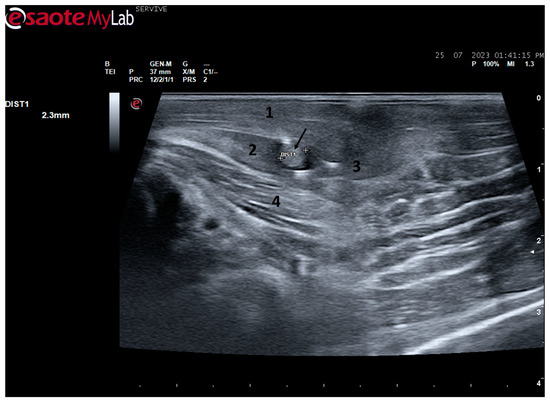

The described technique allows an easy follow-up of the progression of nerve regeneration over time after the induction of a lesion in a controlled surgical environment. For example, after the application of a tube guide, in which the nerve tops of a transected nerve are sutured to the ends of the tube, leaving a gap to be filled inside the biomaterial, immediately after surgery, it is possible to identify the tube guide and the nerve tops inside of it by ultrasound (Figure 9). The tube guide appears as a hyperechogenic structure, at the ends of which the nerve tops are observed (Figure 9a), allowing the measurement of the created gap and its evaluation and measurement over time until the total closure and reconnection of the nerve ends (Figure 9b). In the same way, after the application of end-to-end sutures, in which the ends of the transected nerve are coapted and sutured in order to guarantee their reconnection and anatomical continuity, it is possible to observe the nerve continuity (Figure 10), but at early timepoints after the injury, a small hypoechoic gap appears as a result of the transection. An edema, in association with the inflammatory infiltration resulting from the degenerative phase after the nerve injury, promotes a transient increase in the diameter of the nerve (Figure 10a) that ends up disappearing over time (Figure 10b). In addition to the increase in diameter, due to interstitial edema, the nerve also appears with an increased hyperechogenic appearance. The main advantage of applying ultrasound in the monitoring of nerve regeneration will be to allow the observation of macroscopic morphological changes in the nerve over time, namely changes in its anatomical continuity, in the dimensions of the created nerve gaps, in their diameter, and in the presence or absence of edema and inflammatory infiltrate. Microscopic changes such as endoneurial microvascular degeneration, demyelination/remyelination, and axonal density and reorganization should be later confirmed by more sensitive histomorphometric techniques such as nerve stereology. At the same time, the functional translation of the regenerative process can be evaluated in parallel through functional and behavioral tests, determination of nervous conductivity, and biomechanical and kinematic gait studies.

Figure 10.

Ultrasound image of the left peroneal nerve in a sheep subjected to a transection lesion followed by the application of an end-to-end suture. (a) After 1 week, it is possible to observe that the nerve continuity is still interrupted by a gap between the two nerve tops that have not yet fully reconnected (black arrow). DIST1 represents the nerve diameter, which is enlarged and with an increased hyperechogenic appearance due to interstitial edema and inflammatory infiltrate. (b) After 3 months, the nerve already presents an anatomical continuity, it is less hyperechogenic, and its diameter has decreased considerably (DIST1).